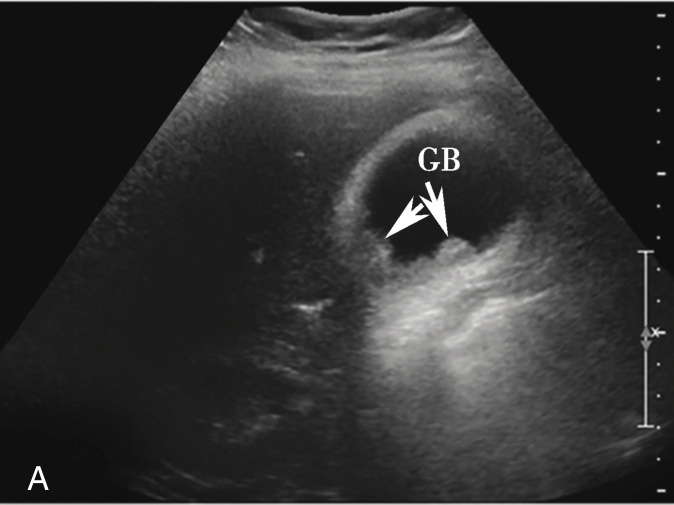

图2-5-1 结节型胆囊癌常规超声图像

A.胆囊壁可见高回声结节,最大径2.8cm;B.CDFI显示结节内可见血流信号